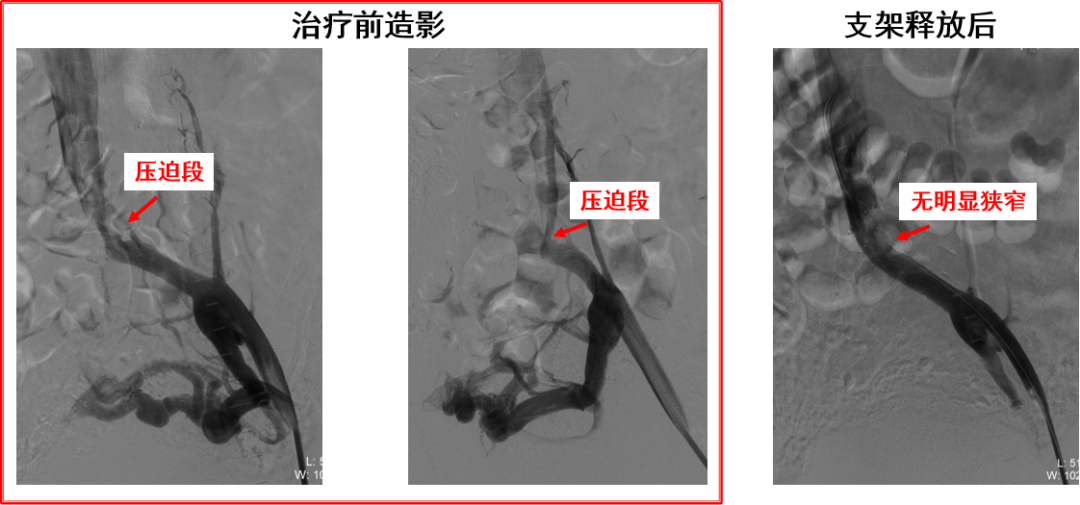

产品C:病例一(柔顺性及贴合性欠佳)

产品C:病例二(髂总静脉远端受压)